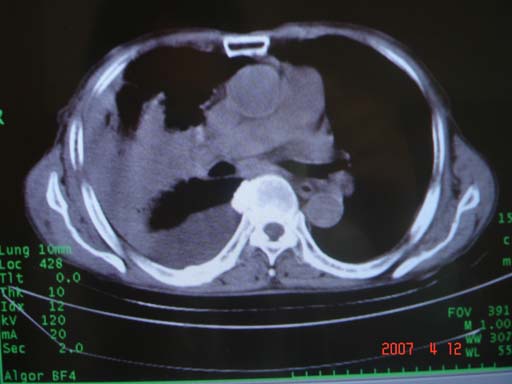

帮我 看看。男77岁咳嗽咯血2月发热2周!病人一般情况可 口痰为鲜红,有点象洗肉水(我看见他吐的痰了)

为何只有这么几幅图像?连纵隔窗都没有。但我发现上叶支气管显示不清,再加上年纪大,咯血等症状,恶性肿瘤首先得考虑。

考虑右肺新生物伴右中上肺阻塞性肺炎及含气不良,右侧胸腔积液。建议痰与纤支镜检查

考虑右侧中央型肺癌伴中上肺阻塞性肺炎、不张,胸腔积液。,建议支纤镜检查。

病灶局限在右肺中上叶,呈大片状实变影,内见空气支气管征,支气管分支较柔软,纵隔内未见肿大淋巴结.支持:感染性病变_1 大叶性肺炎.2 干酪性肺炎.

优先考虑右上肺干酪性肺炎并同侧中叶播散、胸腔积液。分析:右膈肌未见升高、纵隔未见明显右移,胸部各组淋巴结未见可疑肿大,中叶可见支气管铸形,肺野、肺门未见可确定肿块。

单从影像学上来看,该病人应首先考虑,右上肺感染(干酪性肺炎可能大)伴有右侧胸腔积液,理由如下:

1.病灶整体成宽基底征,而未见块状影

2.病灶内的透光区并不是含气支气管征,而像是坏死的肺组织后形成的

3.无肺不张的表现

4.纵隔那未见明显肿大淋巴结

结合病史,该病人尚需作进一步检查胸水,支气管镜,查痰等

右肺上叶实变,实变范围如此之大,如果用肺癌解释的化,应该是比较大的支气管开口发生完全阻塞,但观察上叶前后段支气管还是比较通畅,所以应考虑感染性病变,大叶性肺炎可能,建议抗炎治疗后复查。